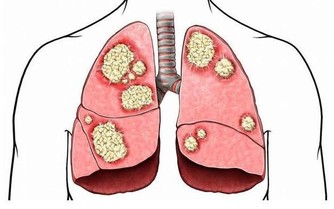

兒童期超重、肥胖會增加高血壓、糖尿病、高甘油三酯、代謝綜合徵等的發生風險,肥胖還會影響兒童青春期發育,危害呼吸系統及骨骼,甚至對心理、行為、認知及智力產生不良影響。